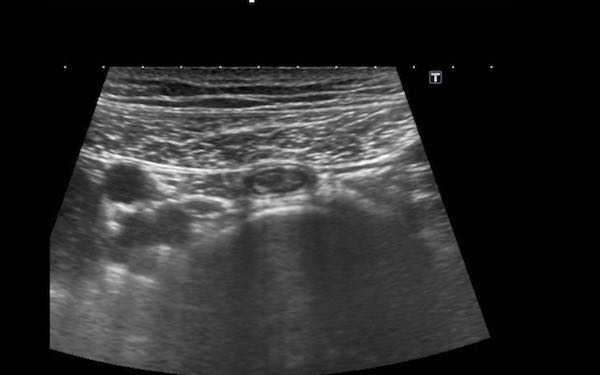

Đây là hình ảnh siêu âm của một trẻ 2 tuổi bị lồng ruột hồi manh tràng từng đợt, được khám trong khoảng thời gian giữa các cơn.

Hồi tràng với nhiều mảng Peyer sa vào manh tràng.

Hình ảnh siêu âm kinh điển của lồng ruột hồi-manh tràng ở hai trẻ khác nhau.

Trong cả hai trường hợp, đoạn hồi tràng bị lồng được định vị không đối xứng bên trong ống lồng ngoài, do mạc treo ruột tăng âm có chứa mỡ, bám vào hồi tràng và đi theo hồi tràng khi bị kéo vào trong.

Trong mạc treo, siêu âm cho thấy một hạch bạch huyết mạc treo (hbh) phóng đại ở cả hai.

Các hạch này phì đại như một phần của tình trạng tăng sản hạch bạch huyết toàn thân và khônghu trú trong lòng hồi tràng.

Do đó đây không phải là điểm dẫn đầu nguyên phát. Ở bệnh nhân bên phải, ruột thừa (mũi tên) cũng bị kéo vào trong.

Lưu ý cấu trúc đa lớp của thành bụng phía trước của phức hợp lồng ruột, đại diện cho ba lớp thành ruột bị gấp lại.